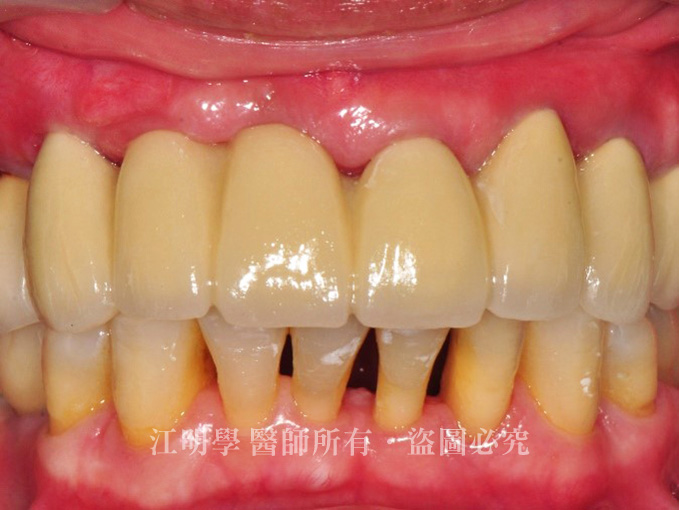

治療後

治療後:咀嚼功能明顯提升

治療後:缺牙問題解決,笑起來更有自信